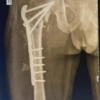

Materials and Methods: We conducted a retrospective case series of 9 consecutive THA cases between March and September 2025. A hybrid ensemble ML system performed pre-operative templating using standardized radiographs with magnification correction. Predictions were systematically validated against actual intraoperative component selections through post-operative analysis. Primary outcomes included component-specific accuracy with descriptive statistics. Secondary outcomes included clinical safety and feasibility assessment.

Nine consecutive patients undergoing primary THA were included. Inclusion criteria were (1) primary osteoarthritis, inflammatory arthritis, or femoral neck fracture requiring THA; (2) high-quality pre-operative anteroposterior pelvis radiographs; (3) complete post-operative radiographic documentation; and (4) minimum 4 weeks follow-up. Exclusion criteria were (1) revision THA; (2) developmental hip dysplasia requiring specialized implants; and (3) inadequate radiographic quality.

Standardized AP pelvis radiographs were obtained using consistent protocols. Magnification correction was applied using calibration spheres, with institution-specific factors ranging from 115% to 132.5%. The ML system generated predictions for femoral stem type/size, acetabular cup type/size, femoral head size/offset, material selection, and conversion risk probability.

Surgical procedures

All procedures were performed by experienced surgeons using standardized approaches. Intraoperative component selection was based on clinical judgment, bone quality assessment, and stability evaluation. Surgical records documented all implant specifications.